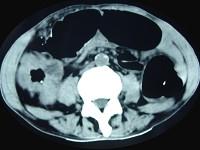

问题 男,70岁,右下腹胀,腹痛,腹泻,影像检查如图,最可能的诊断是 ( )

选项 A、结肠结核 B、结肠淋巴瘤 C、结肠癌 D、结肠套叠 E、结肠克隆恩病

答案 C